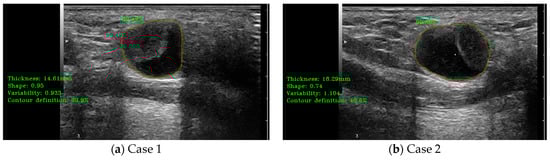

The detection results obtained using the final version of the detection module and the main shape parameters results, including thickness, length, and area, shape form (elliptical vs. circular), shape variability, and the main contour analysis parameter (contour sharpness/definition), are shown in Figure 7.

Figure 7.

(a–d) illustrate cases of lymph node (LN) automatic detection using B-mode ultrasound (US) and shape parameter evaluation. The red contour represents the manually delineated region by the doctor, while the green contour corresponds to the system’s automatically detected LN boundary. The percentage value indicates the detection accuracy.